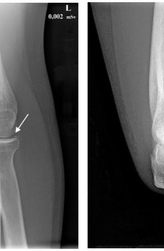

Перелом? Не всегда